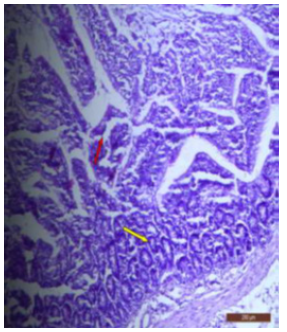

In fluoridated rats damaged and broken villi, focal intervillous haemorrhages and ulceration was present (Figure 12). There was shortening and flattening of some of the villi (Figure 13), distorted crypts, large swollen goblet cells lined by columnar epithelium with wide spaces were present (Figure 14). Distortion of different layers of mucosa with the loss of villous architecture and shedding of surface epithelium was seen in the jejunum of fluoridated rats (Figure 15). The villus architecture was notably disturbed, with a marked loss of crypts. Furthermore, there was a noticeable decrease in the number of goblet cells (Figure 16). The villi appeared scattered and fragmented, indicating a disruption in their typical architecture. Reduction in size of intestinal glands highlighted the detrimental impact of fluoride exposure on the intestinal morphology of rats (Figure 17).

Figure 12: T.S. of jejunum of rat treated with 600 mg NaF/kg b.w./day for 40 days showing ulceration, focal intravillous hemorrhages and broken villi (↑). H&E × 100.

The ileal mucosa of control rat was built up of numerous folds forming the villi, through which connective tissue of the lamina propria containing tubular glands i.e., crypts of Leiberkühn were present (Figure 18). The epithelial lining of the villi was composed of Paneth cells and intestinal glands (Figure 19). In fluorotic rats, there were abnormal shaped, damaged and broken villi with bulbous tips. Lymphatic dilation and haemorrhaged in lamina propria were also seen (Figure 20). In the ileal mucosa, prominent inflammation, distortion of crypts with shredded cells inside the crypts were visible (Figure 21). Swollen and necrotic crypts were present (Figure 22). The ileal tissue showed disruptions in the normal mucosal architecture with signs of villous atrophy and cell infiltration (Figure 23). Lymphatic infiltration was prominent and numerous enlarged lymph nodules appeared in lamina propria of villi. There were ill-defined cell boundaries, vacuolated cytoplasm and pyknotic nuclei (Figure 24).

Figure 13: T.S. of jejunum of rat treated with 600 mg NaF/kg b.w./day for 40 days showing distortion, shortening and flattening of villi (↑). H&E × 100.

Figure 14: T.S. of jejunum of rat treated with 600 mg NaF/kg b.w./day for 40 days showing swollen goblet cells and few nuclei (↑). H&E× 400.

Figure 15: T.S. of jejunum of rat treated with 600 mg NaF/ kg b.w./day for 40 days showing atrophy of villi and distortion of different layers and destruction of surface epithelium (↑). H&E × 100.

Figure 16: T.S. of jejunum of rat treated with 600 mg NaF/ kg b.w./day for 40 days showing disruption of villi (↑), reduction in number of goblet cells (↑) and crypt loss (↑). H&E × 100.

Figure 17: T.S. of ileum of control rat showing scattered and broken villi (↑) and decrease in size of intestinal glands (↑). H&E × 100.